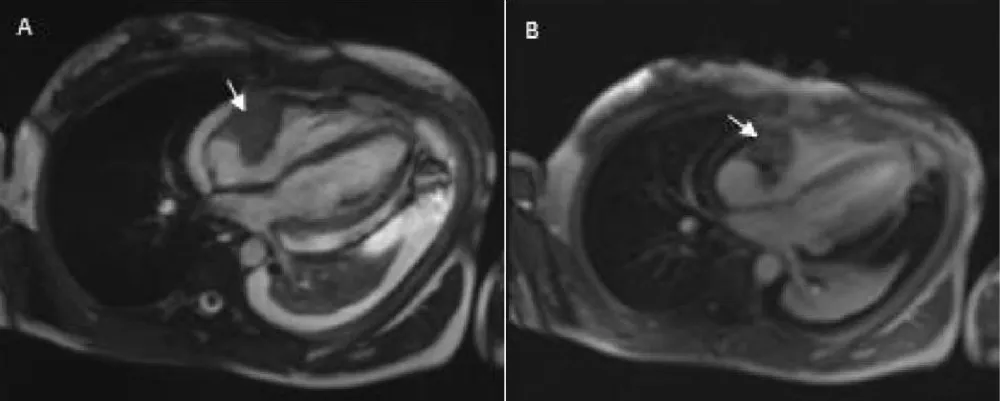

Download Image

Figure 2: Cardiac MRI findings: A: Axial T2-weighted images mass in the right atrium hypointense on T2 with extension into the pericardium and free wall of the right ventricle (arrow) B: Axial T1weighted image after administration of gadolinium shows heterogeneous late enhancement of the right atrial mass (arrow).